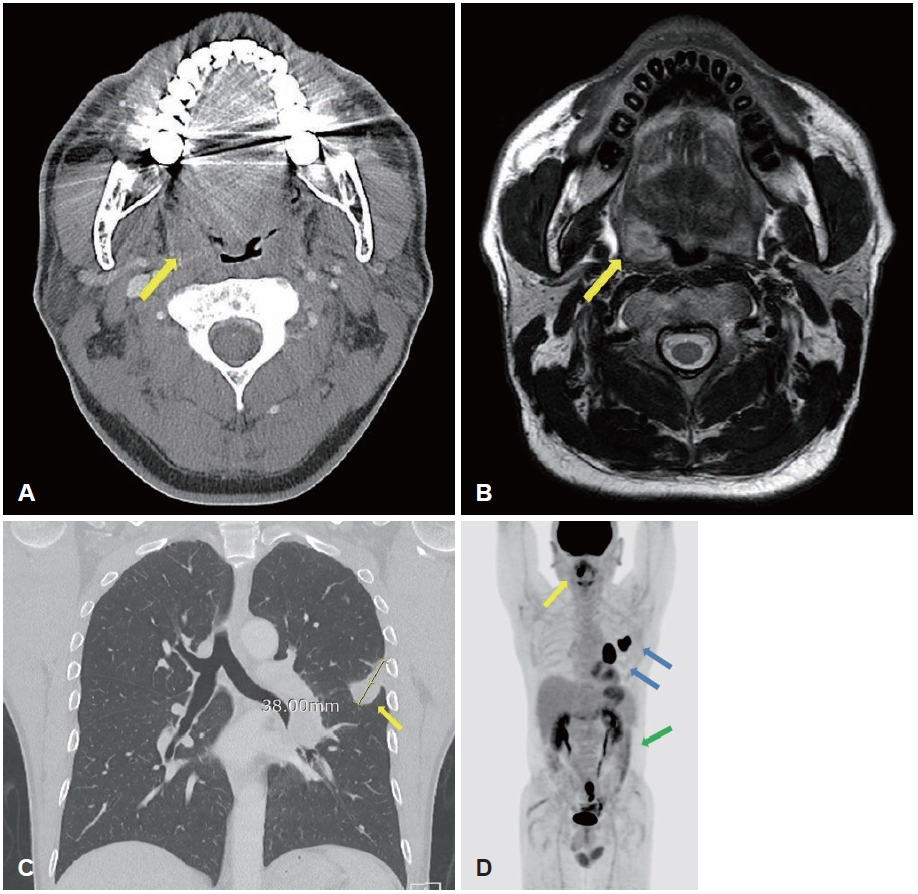

After the second course of radiotherapy during treatment, neck CT showed disappearance of the right tonsillar lesion, and radiotherapy was concluded while immunotherapy was continued. After three cycles of immunotherapy, neck CT showed no residual lesion in the right tonsil (Fig. 4A), and chest CT showed marked reduction in the size of the left primary lung cancer and the metastatic hilar lymph node (Fig. 4B). Abdominal CT also showed resolution of the small bowel lesion previously identified. On outpatient endoscopic re-evaluation, the ulcerative mass previously observed in the right tonsil had resolved and no active mass was identified (Fig. 5). The patient is currently being followed while maintaining immunotherapy.

NotesAcknowledgments This case report was approved by the Institutional Review Board (IRB No.: EUMC 2025-09-061). Author Contribution Conceptualization: Han Su Kim. Data curation: Eun Bin Lee. Investigation: Eun Bin Lee. Methodology: Han Su Kim. Project administration: Eun Bin Lee. Resources: Han Su Kim. Supervision: Han Su Kim. Validation: Han Su Kim. Writing—original draft: Eun Bin Lee. Writing—review & editing: Han Su Kim. Fig. 1.Endoscopic view at the initial outpatient evaluation showing an ulcerative, protruding mass in the right palatine tonsil. Fig. 2.Radiologic findings. A: Contrast-enhanced neck CT showing a 1.8-cm peripherally enhancing, centrally low-density lesion in the right palatine tonsil (yellow arrow). B: Neck MRI showing a 2.3-cm lobulated mass in the right palatine (yellow arrow) tonsil with intermediate T2 signal intensity. C: Chest CT showing a 3.8-cm lobulated mass (yellow arrow) extending across the left major fissure and involving the adjacent pleura. D: PET-CT demonstrating fluorodeoxyglucose uptake in the right palatine tonsil (yellow arrow, SUVmax 21.64), left lower lobe lung lesion (blue arrow, SUVmax 26.41), left hilar lymph node (blue arrow, SUVmax 29.64), and small intestine (green arrow, SUVmax 16.55). Fig. 3.Pathologic findings from the right palatine tonsil biopsy. A: Hematoxylin-eosin–stained specimen showing poorly differentiated carcinoma, favoring metastatic non-small cell lung carcinoma (original magnification ×100). B: Immunohistochemical specimen showing diffuse positivity for cytokeratin pan (CK-PAN), supporting epithelial origin (original magnification ×100). C: Immunohistochemical staining for P40 showing negative results, arguing against a primary squamous cell carcinoma of the tonsil (original magnification ×100). D: Immunohistochemical specimen showing focal vimentin expression, which can be observed in poorly differentiated carcinomas with partial mesenchymal features (original magnification ×100). Fig. 4.Post-treatment radiologic assessment following CCRT. A: Follow-up neck CT showing no residual enhancing mass in the right palatine tonsil (yellow arrow). B: Follow-up chest CT showing a decreased size of the previously noted lobulated mass (yellow arrow) extending across the left major f issure. REFERENCES1. Unsal M, Kutlar G, Sullu Y, Yurtlu S. Tonsillar metastasis of small cell lung carcinoma. Clin Respir J 2016;10(6):681-3.